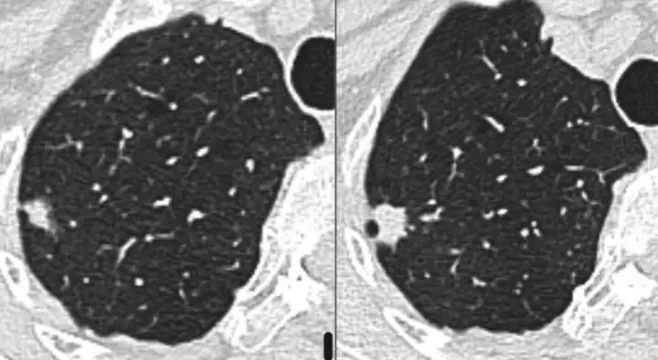

L’intelligence artificielle (IA) appliquée à l’imagerie thoracique dans le dépistage du cancer du poumon intervient à trois niveaux : i) l’aide à la détection de nodules, ii)la caractérisation de la probabilité de malignité du(es) nodule(s) détecté(s) et, iii) l’aide à la prédiction d’apparition du cancer.

Quinze pourcents des personnes qui font l’objet d’un dépistage du cancer du poumon se voient découvrir un nodule de nature indéterminée (NNI) sur le scanner de dépistage. Moins de 15% de ces NNI sont des cancers débutants. Devant un NNI deux attitudes sont proposées : simple surveillance radiologique (une stabilité oriente vers la nature non cancéreuse du NNI) ou abord diagnostique qui n’est pas aisé car il s’agit de toutes petites lésions situées en plein milieu du poumon. Une troisième attitude fait l’objet d’évaluation dans certains centres spécialisés c’est l’administration de traitement préventifs, encore appelée interception du cancer. Nous envisageons de combiner les deux dernières stratégies grâce aux possibilités de l’endoscopie robotisée qui permet la caractérisation histopathologique, immunologique et moléculaire de lésions inaccessibles par les techniques diagnostiques usuelles.